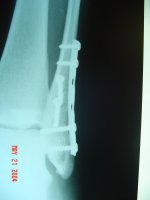

This is all I got.

View attachment 12031

Plate and 6 screws in the left ankle. Never even crashed to win this hardware.